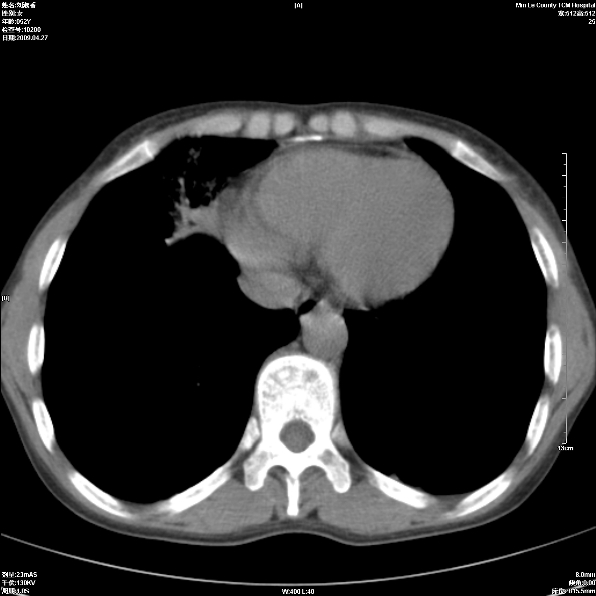

标题: CT19625:女52间断性喀血 [打印本页]

标题: CT19625:女52间断性喀血

考虑右肺中叶感染性病变并右肺中、下叶肺泡积血;建议抗炎、止血治疗后复查。

右肺中叶炎症;右肺中、下叶肺泡积血

右肺中叶支气管扩张并感染或咳血沉积,块右肺中下叶肺泡积血。

右肺中叶慢性炎症伴局部支扩并中下叶肺泡积血。

考虑右肺中叶感染性病变并右肺中、下叶肺泡积血。建议治疗后复查。